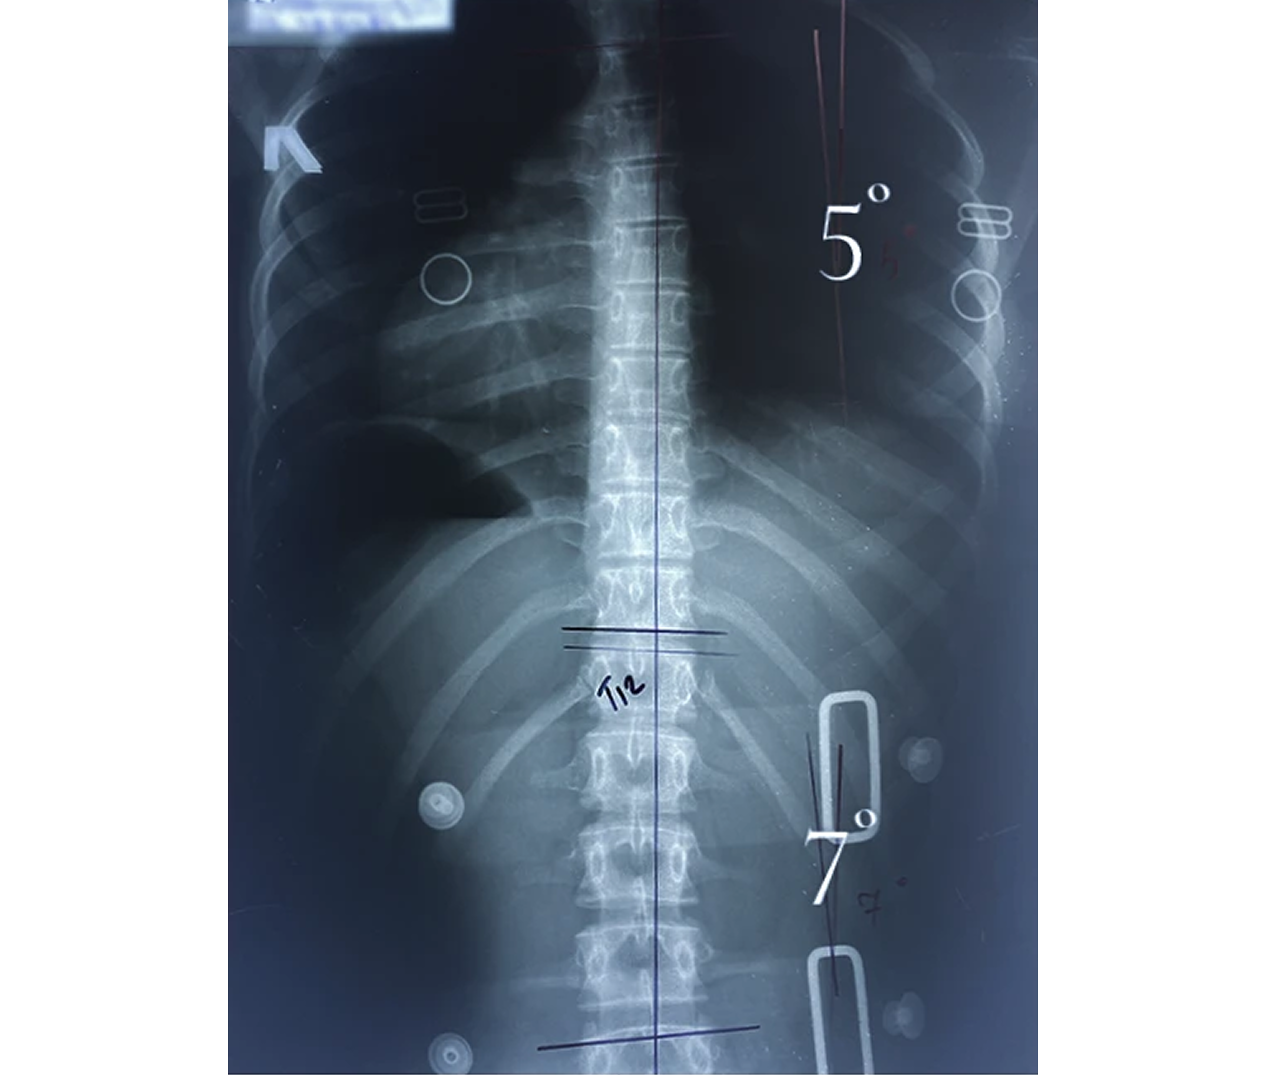

Корсет Шено — это «золотой стандарт» в лечении сколиоза у детей и подростков. В клинике Ортотис Центральная Азия в Алматы мы изготавливаем активные ортопедические корсеты, которые не просто удерживают позвоночник, а эффективно исправляют деформацию.

• Идиопатический сколиоз с углом искривления от 20° по Коббу;